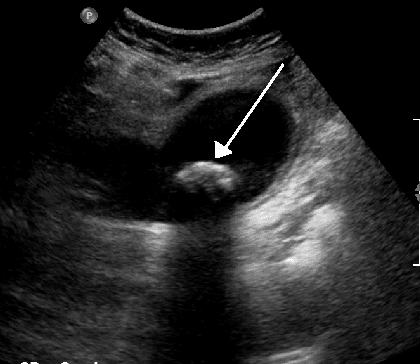

Biliary colic, also known as symptomatic cholelithiasis, a gallbladder attack or gallstone attack, is when a colic (sudden pain) occurs due to a gallstone temporarily blocking the cystic duct. Typically, the pain is in the right upper part of the abdomen, and can be severe. Pain usually lasts from 15 minutes to a few hours. Often, it occurs after eating a heavy meal, or during the night. Repeated attacks are common. Gallstone formation occurs from the precipitation of crystals that aggregate to form stones. The most common form is cholesterol gallstones. Other forms include calcium, bilirubin, pigment, and mixed gallstones. Other conditions that produce similar symptoms include appendicitis, stomach ulcers, pancreatitis, and gastroesophageal reflux disease. Treatment for gallbladder attacks is typically surgery to remove the gallbladder. This can be either done through small incisions or through a single larger incision. Open surgery through a larger incision is associated with more complications than surgery through small incisions. Surgery is typically done under general anesthesia. In those who are unable to have surgery, medication to try to dissolve the stones or shock wave lithotripsy may be tried. it is not clear whether surgery is indicated for everyone with biliary colic. In the developed world, 10 to 15% of adults have gallstones. Of those with gallstones, biliary colic occurs in 1 to 4% each year. Nearly 30% of people have further problems related to gallstones in the year following an attack. About 15% of people with biliary colic eventually develop inflammation of the gallbladder if not treated. Other complications include inflammation of the pancreas. Pain is the most common presenting symptom. It is usually described as sharp, crampy, dull or severe right upper quadrant pain, which may radiate to the right shoulder, or less commonly, behind the breastbone. Nausea and vomiting can be associated with biliary colic. Individuals may also present with pain that is induced following a fatty meal and the symptom of indigestion.